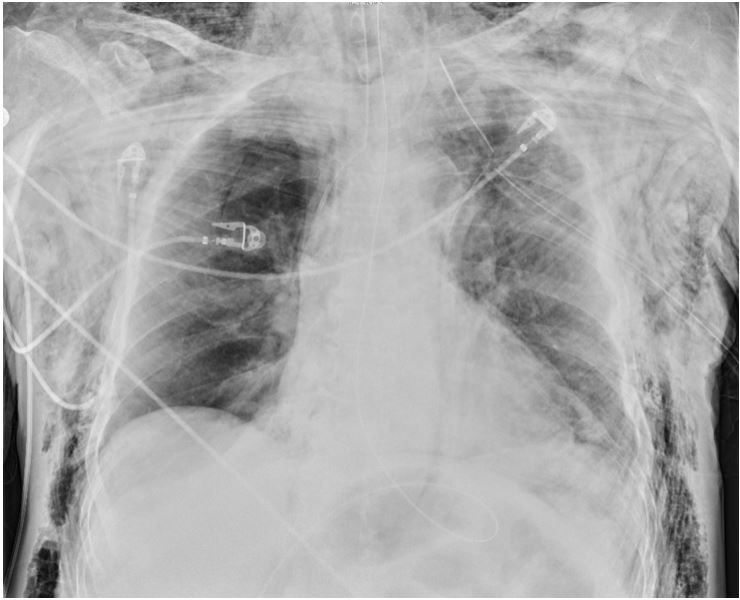

A 55 year old male presents to the ED in respiratory distress with hypoxia, tachycardia, and tracheal deviation. The patient is stabilized after intubation and chest tube insertion. A CXR is done. What's the diagnosis? (scroll down for answer)

Answer: Subcutaenous emphysema

- The radiographic 'ginkgo leaf sign'- air outlines the fibers of the pectoralis major muscle, forming a streaky pattern similar to branching pattern in veins of a ginkgo leaf

- Highly suggestive of an underlying pneumothorax (or a tracheo-bronchial injury)

- Exam will reveal chest wall crepitance

- The diffuse nature of the emphysema suggests need for bronchoscopy to evaluate for tracheo-bronchial injury